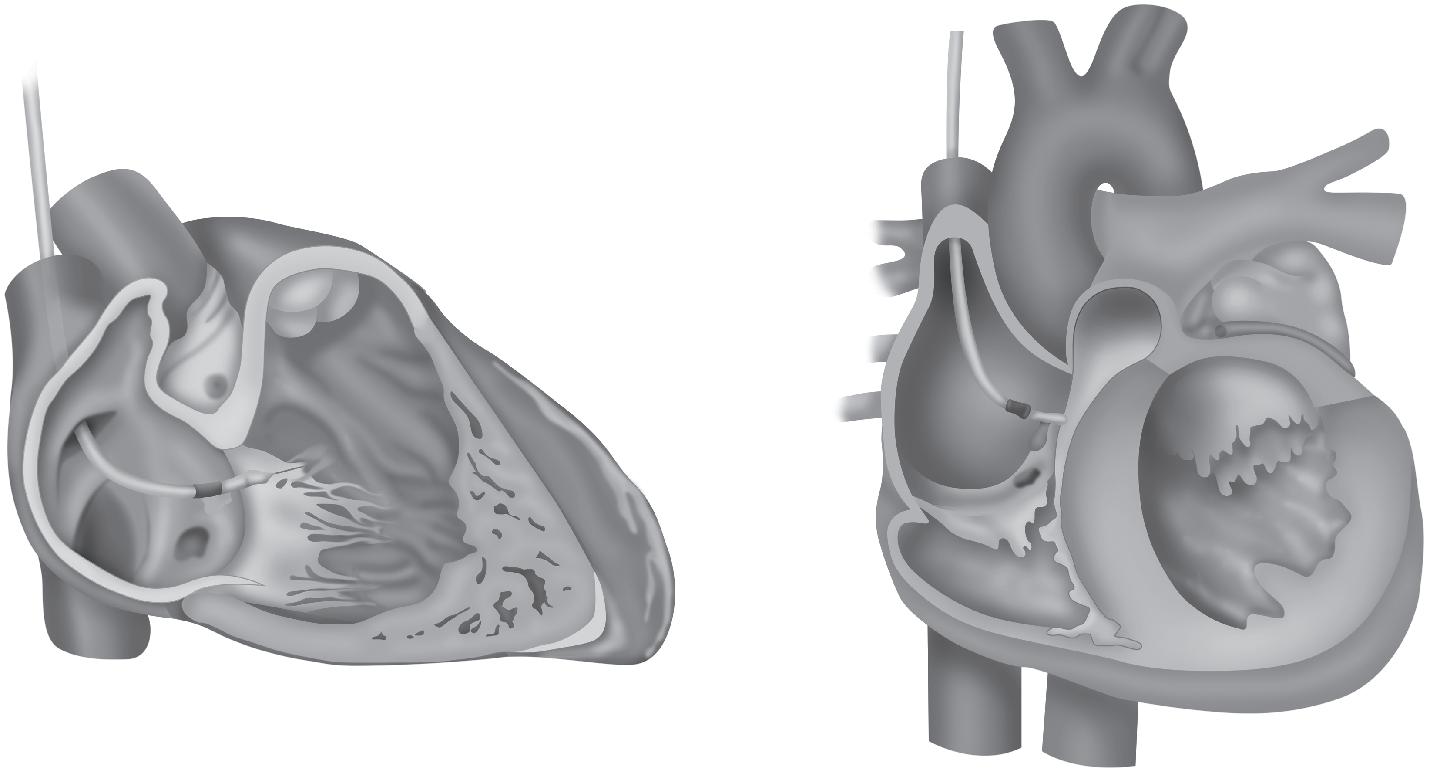

15 Marca-passo Provisório, Definitivo, Ressincronizadores e Desfibriladores, 145 Julianny Freitas Rafael Magacho • Vicente de Paulo Fernandes do Nascimento • Amanda Mendonça da Silva Costa • Nathália Rodrigues da Silva • Gustavo Luiz Gouvêa de Almeida Jr.